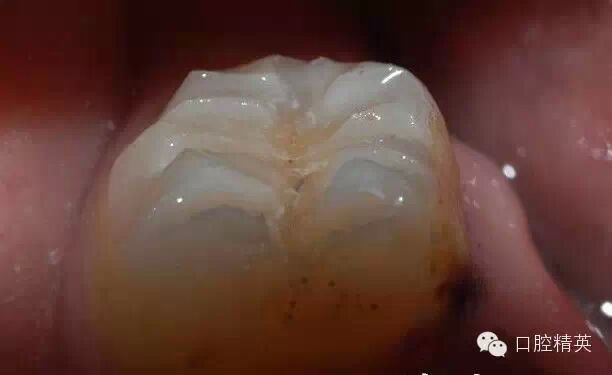

咬合時(shí)的情況